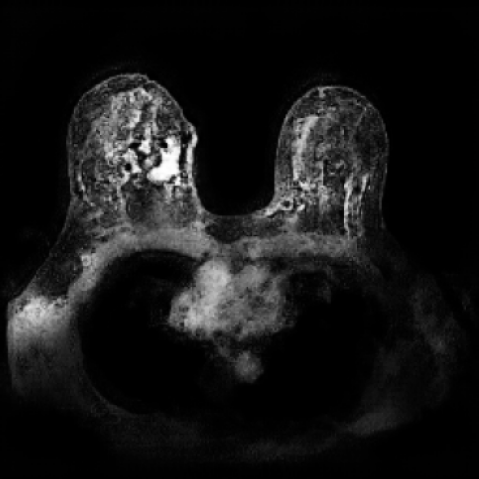

To demonstrate the advantages of 3D semantic image synthesis over 2D semantic semantic image synthesis, we conducted a detailed comparison with the SegGuidedDiff [26] model. SegGuidedDiff generates medical images based on 2D semantic maps, producing individual 2D slices that are later stacked to form a 3D image. However, this approach has limitations in capturing spatial continuity and coherence across slices, which is critical for representing the spatial structure of 3D medical images. As a result, inconsistencies often arise between different slices, particularly in preserving anatomical structures across the coronal and sagittal planes. The generated images exhibit varying levels of denoising, resulting in differences in brightness and sharpness across the images. This inconsistency in denoising can lead to noticeable variations in visual quality, where some regions appear clearer and others less distinct.

As shown in Figure 5, the generated slices exhibit high consistency across adjacent slices. The anatomical structures and semantic patterns are smoothly and coherently preserved between slices, indicating that our model is capable of generating 3D-consistent synthetic images rather than isolated 2D slices.

In contrast, the segmentation result of synthetic data generated by SegGuidedDiff using 2D semantic map slices shows significantly lower performance (Dice = 0.602). Notably, SegGuidedDiff generates images slice-by-slice in 2D without modeling the full 3D spatial context. As a result, the synthesized volumes often suffer from inter-slice inconsistencies and unrealistic spatial structures, which negatively impact the downstream segmentation performance.

Figure 8 further supports these findings: the images generated by Med-LSDM preserve spatial coherence across coronal and sagittal planes, whereas those from SegGuidedDiff show noticeable inconsistencies. These artifacts likely result from the 2D nature of SegGuidedDiff, which fails to account for 3D spatial relationships. In contrast, our model’s volumetric diffusion framework inherently preserves anatomical consistency, highlighting its advanta in synthesizing high-fidelity 3D medical images.